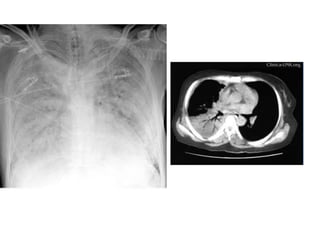

• #51 Paciente masculino de 63 años que refiere tos, disnea y dolor torácico derecho de aproximadamente siete días de evolución. El examen físico revela hipo ventilación en hemitorax derecho. Como dato positivo de laboratorio presenta VSG aumentada. Se solicita inicialmente una radiografía de tórax frente en la cual se observa, radioopacidad basal derecha con broncograma aéreo que borra el seno costofrénico homolateral. Engrosamiento pleural difuso que impresiona comprometer pleura mediastínica. Dados los hallazgos en la radiografía se decide ampliar el diagnostico solicitándole una TAC de tórax con contraste endovenoso en la cual se observa engrosamiento circunferencial pleural de hemitorax derecho. Atelectasia de segmentos inferiores con broncograma aéreo. Pequeña área líquida tabicada. Adenomegalias mediastinales en región prevascular, pretraqueal retrocavo y ventana aortopulmonar. Caja torácica sin alteraciones tomográficamente demostrables. Estructura y densitometría osteoarticular de l raquis dorsal normal. DIAGNOSTICOS DIFERENCIALES: • Engrosamiento pleural: Derrame organizado, hemotórax, piotorax, cirugía previa, radioterapia, exposición al Asbesto. • Tumores Benignos: lipomas, tumores fibrosos, esplenosis torácica. • Tumores malignos: MTTS de pulmón, mama, linfoma. • Mesotelioma maligno. DIAGNOSTICO DEFINITIVO: • MESOTELIOMA MALIGO